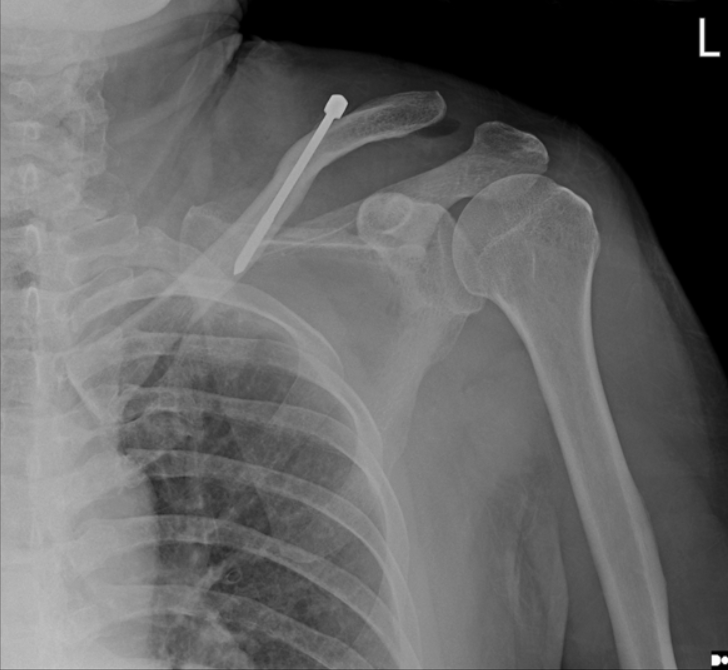

(A)在c臂图像增强器的帮助下,用克氏针将锁骨推入解剖位置进行闭合复位。(B)从肩峰尖端穿过肩锁关节(ACJ)至锁骨远端,用Knowles钉在锁骨远端后侧实现皮质锚定。采用Knowles销固定时,采用拉力螺钉技术保持ACJ空间。(C)术后x线片显示经皮Knowles针闭合复位治疗ACJ脱位复位良好。